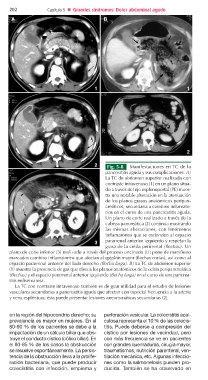

2 Fig. 5-8 Manifestaciones en TC de la

pancreatitis aguda y sus complicaciones. A)

La TC de abdomen superior realizada con

contraste intravenoso (1) en un plano situa-

do a través del eje esplenoportal (PE) mues-

tra una notable alteración en la atenuación

de los planos grasos anatómicos peripan-

creáticos, secundaria a cambios inflamato-

rios en el curso de una pancreatitis aguda.

Un plano de corte realizado a través de la

cabeza pancreática (2) continúa mostrando

las mismas alteraciones, con fenómenos

inflamatorios que se extienden al espacio

3 pararrenal anterior izquierdo y respetan la

grasa de la celda perirrenal (flechas). Un

plano de corte inferior (3) realizado a través del proceso uncinado (U) pone de manifiesto

marcados cambios inflamatorios que afectan al epiplón mayor (flechas cortas), así como al

espacio pararrenal anterior del lado derecho (flecha larga). B) La TC de abdomen superior

(1) muestra la presencia de gas que diseca los planos anatómicos de la celda peripancreática

(flechas) y el espacio pararrenal anterior izquierdo (flecha larga) en el curso de una pancrea-

titis enfisematosa.

La TC con contraste intravenoso también es de gran utilidad para el estudio de lesiones

vasculares secundarias a pancreatitis aguda que afectan con especial frecuencia a la arteria

y vena esplénicas; ésta puede presentar lesiones aneurismáticas secundarias (2).